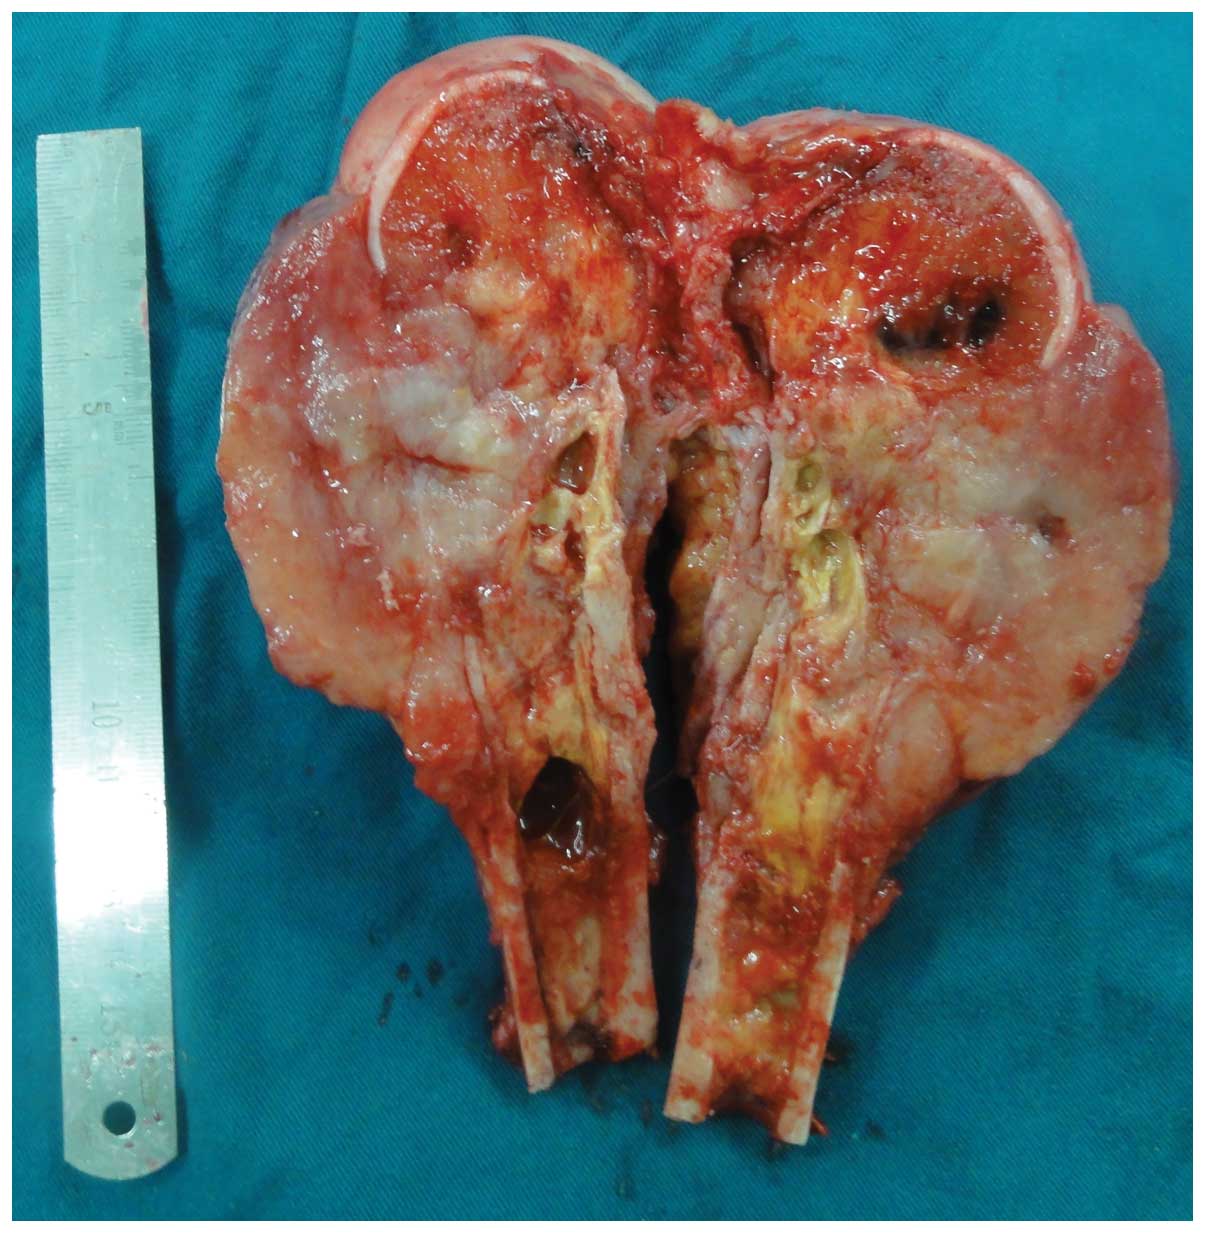

A limb-salvage procedure, involving a wide resection

and a total knee endoprosthesis replacement, was performed in May

2012. Examination of the resection specimen showed a soft,

light-yellow (or gray), gelatinous tumor measuring 13 cm along the

long axis of the femur and 6 cm transversely. The tumor was

centered in the distal part of the femur, with involvement of the

surrounding soft tissues. A central hemorrhagic and necrotic area

contained serosanguineous fluid, with an abundant local blood

supply (Fig. 5). No intra-articular

extension was observed and there was no indication of regional

metastasis on dissection of the popliteal fossa lymph nodes. The

patient’s postoperative course was uneventful.